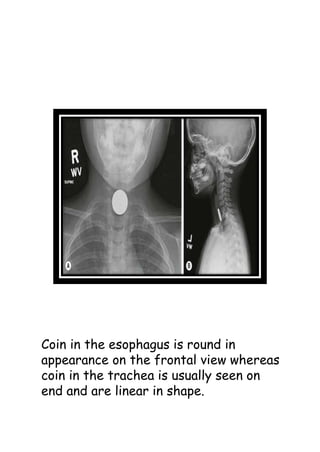

Coin in the esophagus is round in

appearance on the frontal view whereas

coin in the trachea is usually seen on

end and are linear in shape.